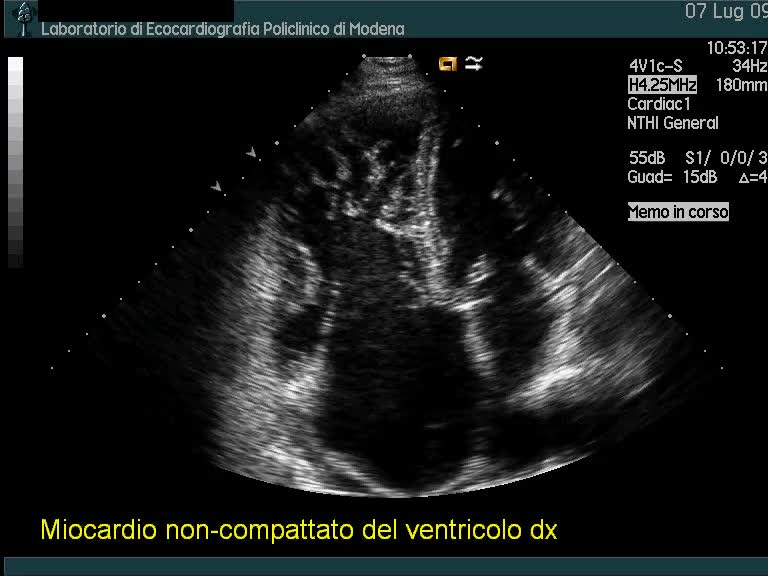

Miocardio non-compattato del ventricolo destro

Autore:

Andrea Barbieri